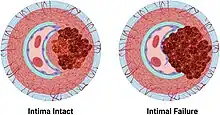

By separating a portion of the wall of the artery (a layer of the tunica media or in some cases tunica intima), a tear creates two lumens or passages within the vessel, the original or true lumen, and the false lumen created by the new space within the wall of the artery. It is not yet clear if the tear in the innermost layer, the tunica intima, is secondary to the tear in the tunica media. Dissections originating in the tunica media are caused by disruption of the vasa vasorum. It is thought that dysfunction in the vasa vasorum is an underlying cause of dissections.[2]

Arterial dissections become life-threatening when growth of the false lumen prevents perfusion of the true lumen and the related end organs. For example, in an aortic dissection, if the left subclavian artery orifice were distal to the origin of the dissection, then the left subclavian would be said to be perfused by the false lumen, while the left common carotid (and its end organ, the left hemisphere of the brain) if proximal to the dissection, would be perfused by the true lumen proximal to the dissection.

Vessels and organs that are perfused from a false lumen may be well-perfused to varying degrees, from normal perfusion to no perfusion. In some cases, little to no end-organ damage or failure may be seen. Similarly, vessels and organs perfused from the true lumen but distal to the dissection may be perfused to varying degrees. In the above example, if the aortic dissection extended from proximal to the left subclavian artery takeoff to the mid descending aorta, the common iliac arteries would be perfused from the true lumen distal to the dissection but would be at risk for malperfusion due to occlusion of the true lumen of the aorta by the false lumen.